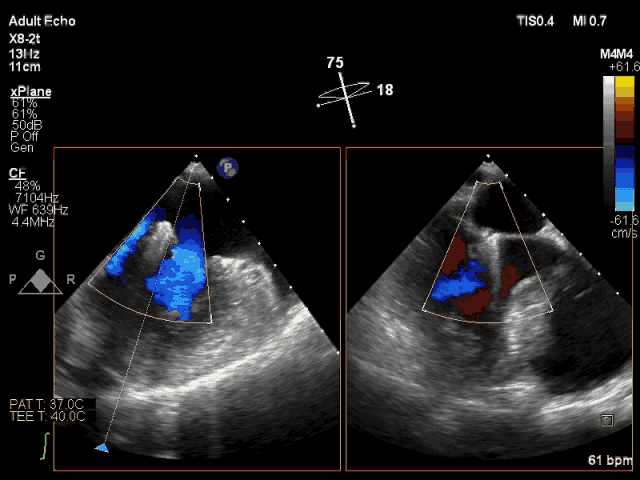

夹合即刻CDFI示轻微MR

ValveClamp二尖瓣夹合术是一种“在跳动的心脏上完成的超微创手术”,先在心前区切开3cm切口,在心脏超声指导下穿刺心脏送入器械进行手术操作。由于其输送系统型号更小,捕获范围更大,适应证更广,操作更简便,所以导管操作时间仅为国外五分之一。

此次转播心脏超声机器为最新一代Philips EPIQ 7C,使用X8-2t食道探头进行术中经食道超声,采用TrueVue实时三维双容积视野同时显示二尖瓣左房观和左室观。新一代超声机器分辨率高、图像处理速度快、图像界面舒适,使得手术非常顺利,手术转播的导管操作时间仅用8分钟。患者术后即刻效果满意,反流从重度减少到轻度。